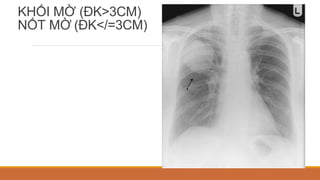

CÁC DẠNG TỔN THƯƠNG NHU MÔ PHỔI

KHỐI MỜ (ĐK>3CM)

NỐT MỜ (ĐK</=3CM)